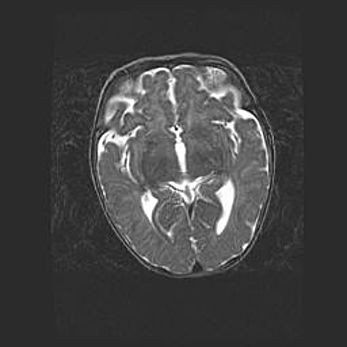

Сообщающаяся гидроцефалия. Кистозная энцефаломаляция головного мозга.

Возраст: 3 месяца 4 дня

Вес: 3100 г

Пол: женский

Окружность головы: 34 см

Срок гестации: 31 неделя

Кистозная энцефаломаляция головного мозга - одна из форм поражения головного мозга в детском возрасте. Характеризуется возникновением множественных и распространённых кист в коре, белом веществе и подкорковых образованиях головного мозга у плодов, новорождённых и детей раннего возраста. Развитие кистозной энцефаломаляции связано с внутриутробной асфиксией и гипотонией, родовой травмой, тромбозом синусов, пороками развития сосудов, инфекциями, сепсисом и другими причинами. Наиболее значимые инфекционные агенты: вирусы простого герпеса, цитомегалии, краснухи, токсоплазмы, энтеробактерии, золотистый стафилококк и другие.